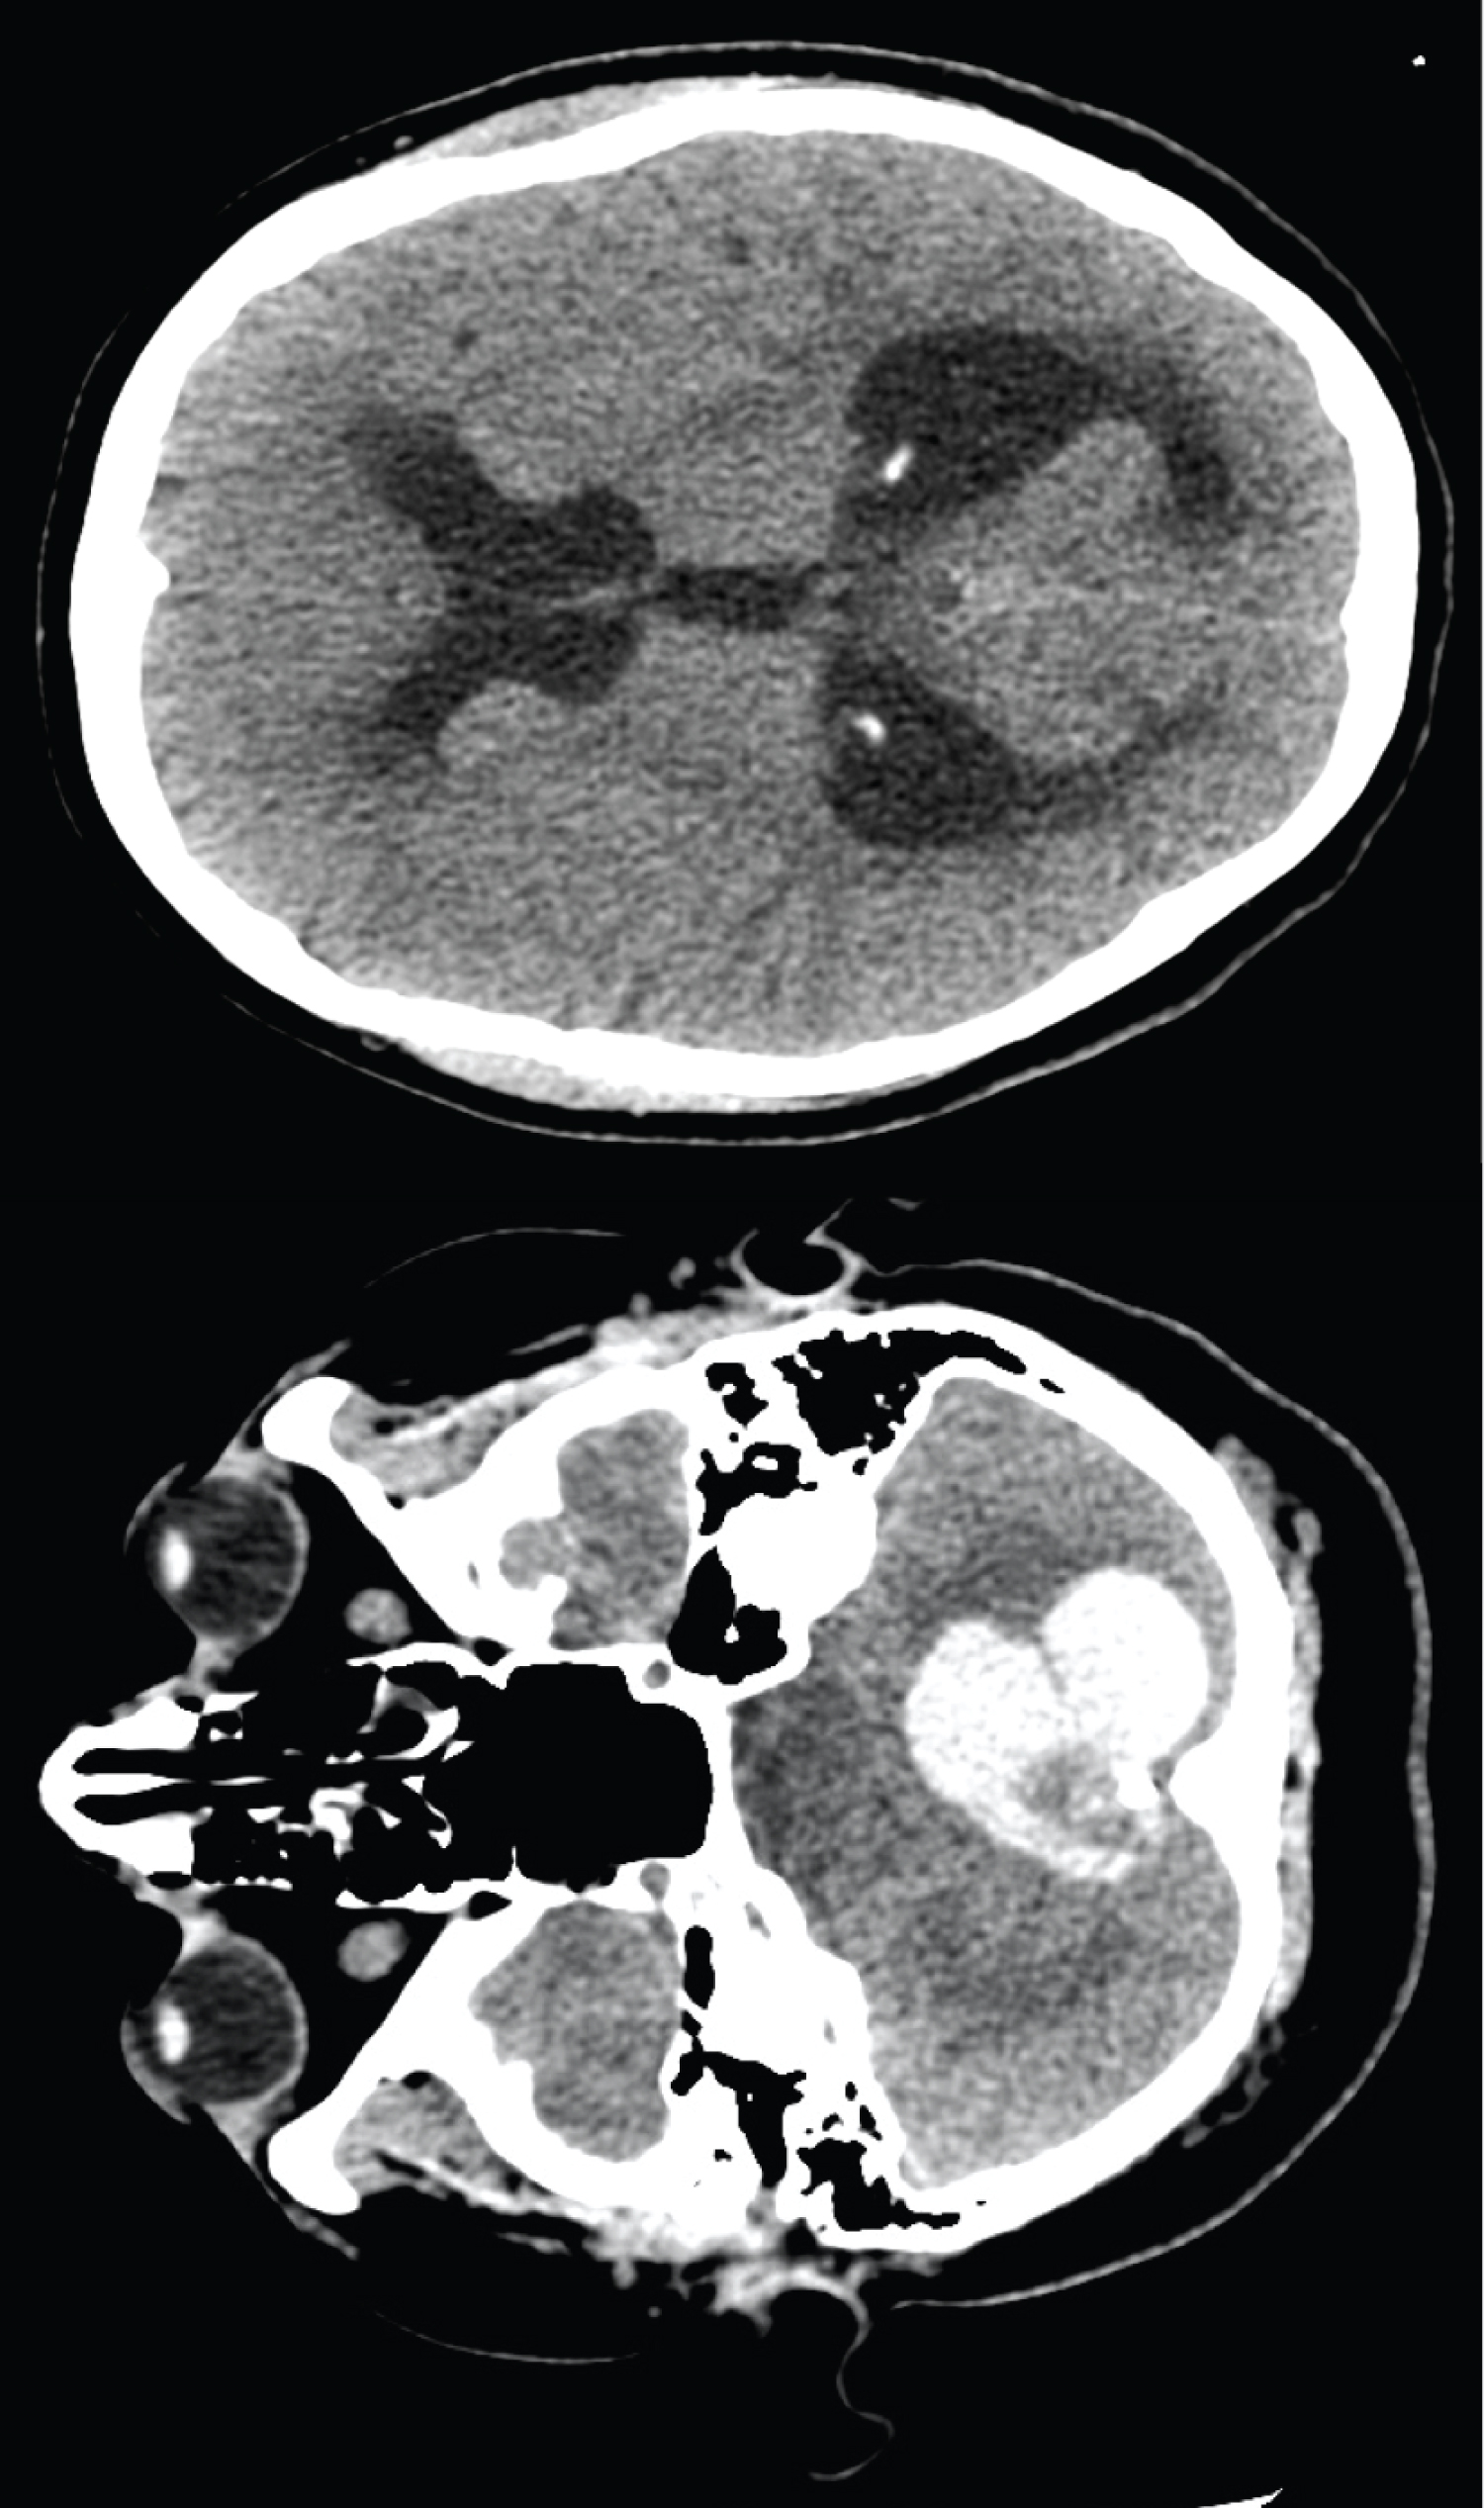

CT brain (Figure 1) illustrated a well-defined hyperdense lesion in the posterior fossa within which was foci of calcification, and secondary acute obstructive hydrocephalus. Spontaneous haemorrhage secondary to a vascular lesion was suspected due to the hyperdensity of the lesion and the presence of calcification. She underwent urgent external ventricular drainage (EVD), leading to resolution of her VIth nerve palsies and headache.

Figure 1: Pre-operative CT imaging (A) Axial CT through posterior fossa showing hyperdense lesion with central calcification; (B) Axial CT through lateral ventricles showing acute hydrocephalus. View Figure 1